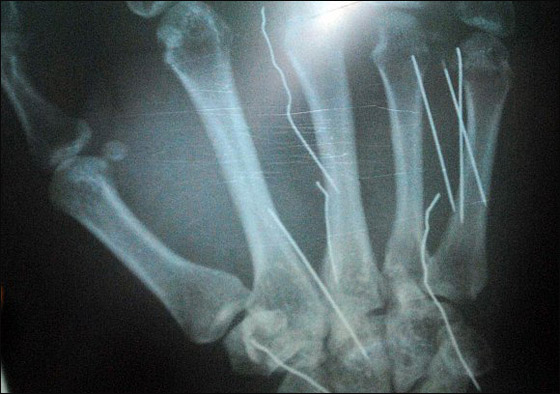

واتهمت الخادمة ليشامي (38 عاماً) كفيلها بغرس مسامير حجمها 3.5 سم في يديها وساقيها بمساعدة زوجته التي كبلتها بعد تعذيبها. وذكرت السلطات السيريلانكية أن خادمة قادمة من الكويت خضعت لجراحة عاجلة لاستخراج المسامير التي وجدت في جسدها، حيث استُخرجت تسعة مسامير، فيما ستجرى عملية جراحية أخرى لها لاستخراج المسامير المتبقية، مشيرة إلى أن القضية ما زالت قيد التحقيق.

يشار إلى أن خادمة سيريلانكية كانت قد اتهمت في شهر أغسطس الماضي كفيلها السعودي وزوجته بتعذيبها وغرس 24 مسماراً في مواقع مختلفة من جسمها، إلا أن التحقيقات لم تثبت صحة أقوالها رغم مرور أربعة أشهر على هذه الحادثة.